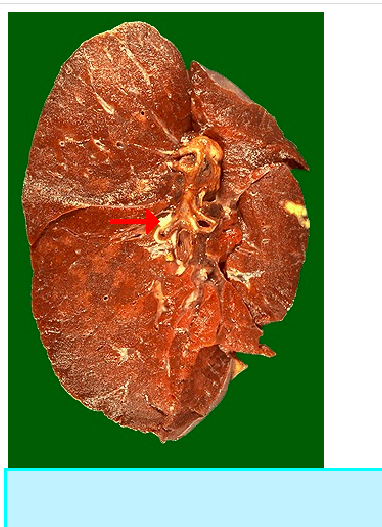

What does this arrow depict? [1]

A

Ghon complex

Which pathogen causes this diease? [1]

TB: ghon complex